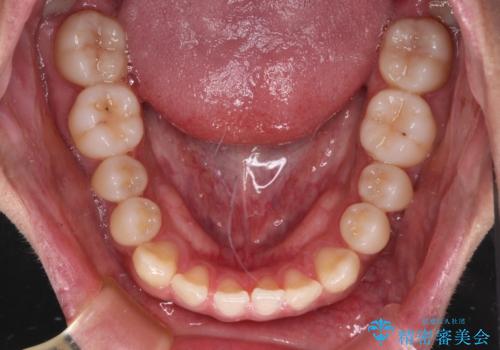

- 前歯のクロスバイトを気にして来院された患者様です。

1年半後に結婚式が控えているとのことで、ワイヤー矯正で早めに治療を終えることを希望されました。

骨格的に下顎が前方に位置していましたが、歯列矯正で改善できると判断し、ワイヤー装置にて矯正治療を行うこととしました。

骨格的な左右差も顕著であったため、正中は合わず、上下前歯の一部が接触しない咬み合わせとなることが予想されましたが、正中はもともとのズレが小さかったことから、合わせることができました。

治療期間も10か月間という短期間で終了し、患者様には大変満足していただきました。